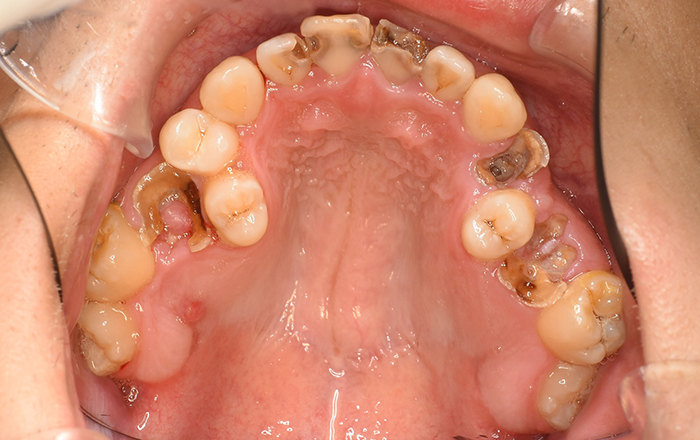

むし歯がある場合は、矯正前に全てのむし歯治療を終わらせる必要があります。

むし歯がある場合、治療してからでないと矯正を始められない理由は下記の通りです。

・むし歯の箇所に装置が付けられない

・むし歯を放置しておくと、感染してむし歯になりやすくなる

・むし歯になった歯は、自然治癒せず、さらに進行する可能性があるため

むし歯の数が多い場合は、スタートのタイミングが少し遅くなってしまう可能性があるので、矯正を考えていらっしゃる方は、事前にむし歯を早期治療しておきましょう!